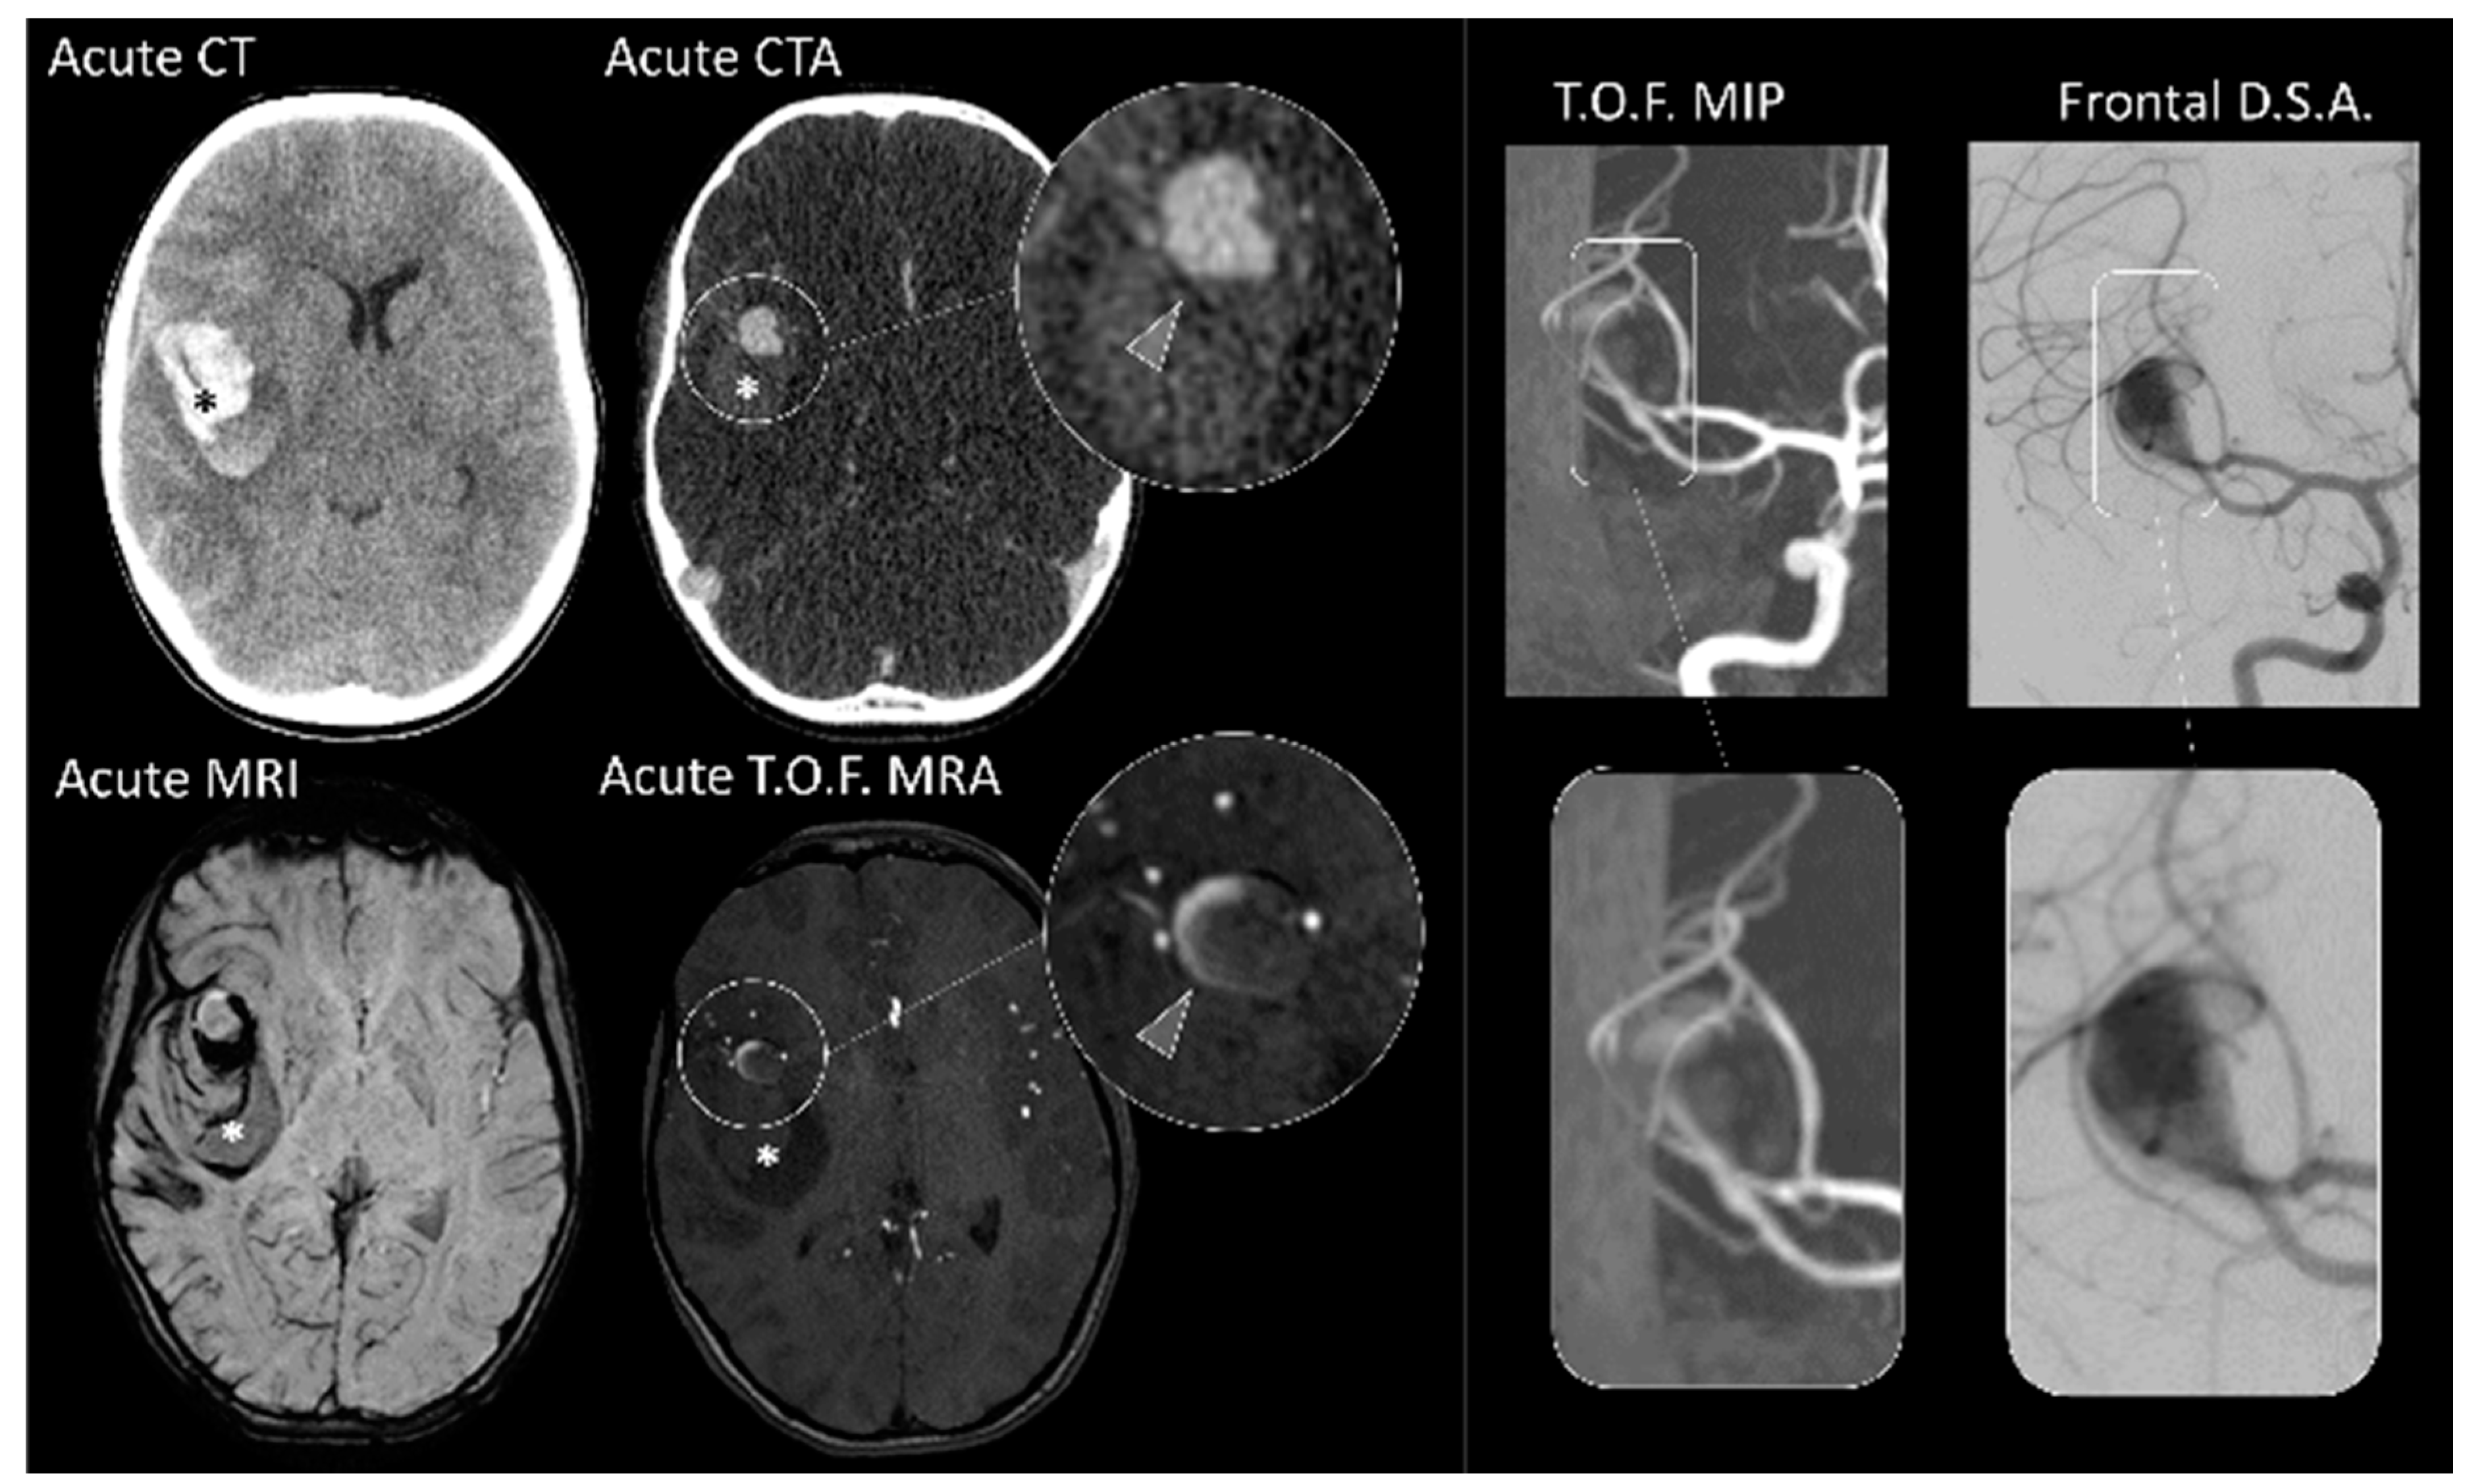

As arteriovenous shunts are the most prominent cause for hemorrhage in children, perfusion imaging such as arterial spin labelling, and dynamic vascular imaging such as time-resolved multiphase MR-angiography can give immediate insight on the underlying etiology and help tailor therapeutic management (See Figure 3—Advanced imaging)

Arterial spin labelling is a MR based non-contrast perfusion technique that has been shown to identify areas of high cerebral blood flow in pediatric AVMs with good sensitivity [23]. Quantifying its added value in the routine acute evaluation of pediatric ICH is an unmet need, but it is a useful and easy-to-use adjunct in clinical practice.

Similarly, dynamic MR-angiography can provide key information with regards to the presence of an arteriovenous shunt, as well as an accurate preliminary delineation of arterial feeders, nidus sectors, venous outflow and their respective angiodynamics.

The timing of repeat imaging should be tailored to specific clinical context and should include repeat DSA. Common temporal landmarks include after mass effect contraction (within three weeks), and after complete hemorrhage resorption (within three to six months) if intermediate control remained inconclusive.

Figure 3. Advanced imaging. MRI images of a 5-year-old girl presenting with acute headaches and confusion. The top row shows an early subacute intracerebral hemorrhage (Arrowhead, HypotT2* and HyperT1) with no detectable vascular anomaly on the TOF sequence. DSA was also found to be normal at that time. The bottom panels show the imaging appearance 4 months thereafter; with increased cerebral blood flow (CBF) within a vascular nidus (Arrowhead) seen on the ASL sequence, post contrast T1, and TOF. Dynamic MRA shows early enhancement of cerebral veins and a nidus within the parenchyma characterizing a brain arteriovenous malformation (AVM), confirmed on the DSA acquired the next day.